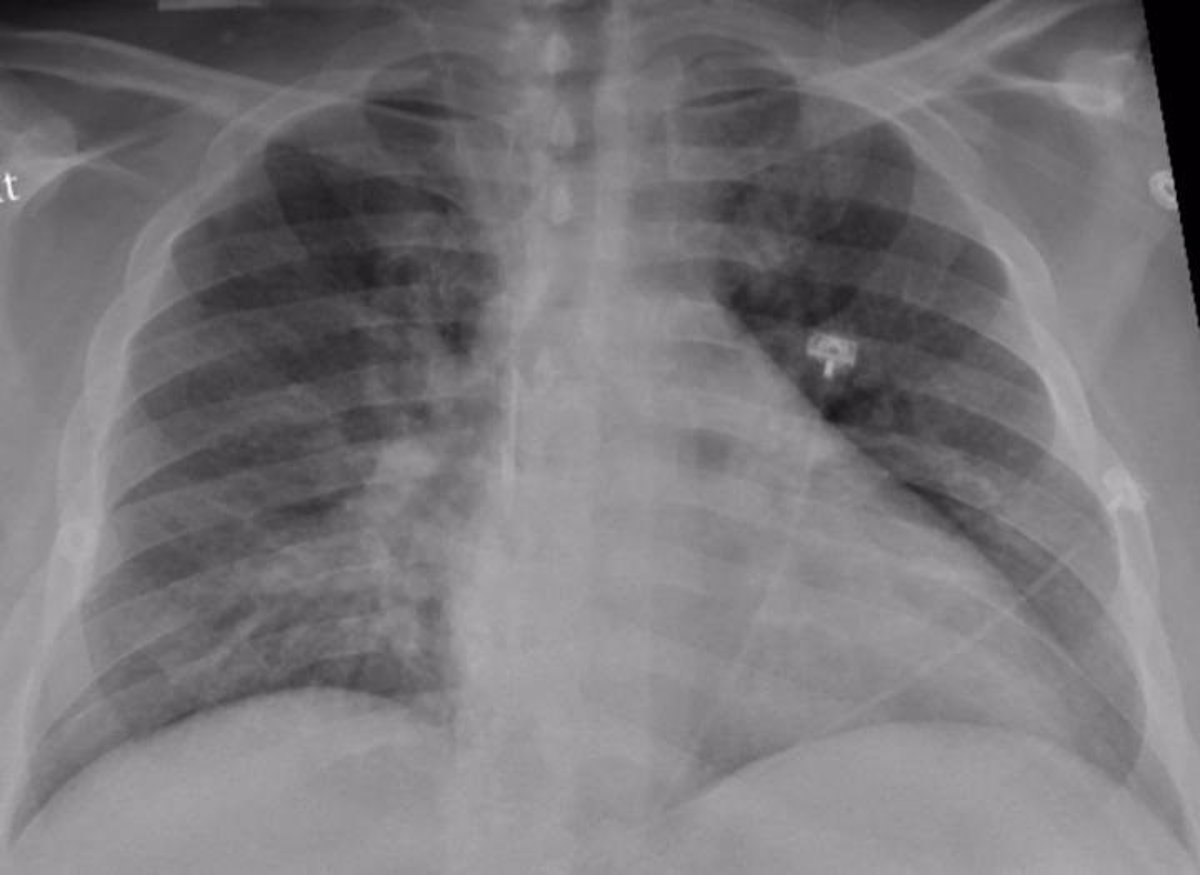

Esta enfermedad, poco frecuente en México pero con una alta tasa de mortalidad, ocasiona una fibrosis pulmonar permanente, que tiene como consecuencia dificultades para respirar y, por tanto, una disminución de la cantidad de oxígeno que reciben los pulmones y que envían al resto de los órganos y tejidos.

EsSalud advirtió hoy que la aparición de la fibrosis pulmonar es silenciosa, y que, al no ser detectada a tiempo, deteriora la función respiratoria hasta causar la muerte.

La fibrosis pulmonar idiopática es una enfermedad progresiva en la que se van produciendo cicatrices en ambos pulmones que dificultan el intercambio de oxígeno y provocan tos crónica y disnea o falta de aire.

No hay otras manifestaciones propias de la enfermedad, aunque pueden estar presentes las debidas a la asociación de comorbilidades como hipertensión pulmonar, enfisema, síndrome de apneas hipoapneas del sueño, cáncer de pulmón o RGE1,2. Los médicos de familia estamos acostumbrados a diagnosticar y tratar enfermedades pulmonares crónicas como la EPOC y el asma debido a su alta prevalencia en nuestras consultas, pero es importante realizar un diagnóstico diferencial ante pacientes con disnea que tras descartar estas 2 enfermedades obstructivas pueden presentar otras enfermedades respiratorias menos frecuentes o raras. Se define como un rápido deterioro de la enfermedad en ausencia de infección respiratoria, insuficiencia cardíaca, embolismo pulmonar o cualquier otra causa identificable.